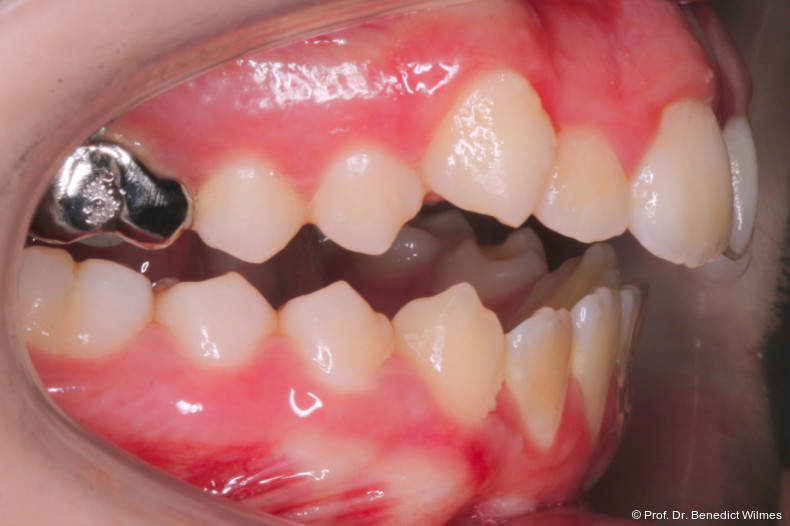

Eine 13-jährige Patientin stellte sich mit beidseitigem Kreuzbiss, einem anterioren offenen Biss und einer Angle Klasse II vor. Das viszerale Schluckmuster wurde mittels logopädischer Maßnahmen umgestellt, der offene Biss persistierte jedoch (Abb. 3a–l).